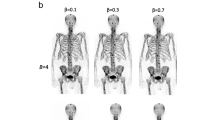

Generation of a whole-body SUV error map

Whole-body maps showing the percentage differences in SUV between PET images reconstructed using the modified AC map (PETAC-Mod) and the standard AC map (PETAC-St) were generated using the following formula: (PETAC-Mod − PETAC-St)/PETAC-St × 100 %. The resulting difference map was analysed for body regions showing the largest differences in SUV.

Analysis of the whole-body error maps showed that the largest errors with an average of 15–20 % were present in bone (Figs. 3 and 4). In the soft tissues the highest SUV errors were seen in the brain and tissues just adjacent to the bones (10–15 %) with a rapid decrease in error magnitude with distance from bone. Errors in other areas of the body SUV error maps were generally below 5 %. In addition to areas of underestimation, regions of slight overestimation of SUV were also identified in soft tissue on the SUV error maps (Fig. 3), but again not exceeding 5 %. Bone lesions and soft-tissue lesions adjacent to bone were quantitatively assessed for SUV errors (Table 2). Quantitative analysis of brain lesions was not performed as the focus was on body imaging and our series contained only a single patient with a brain lesion. In Fig. 4, axial images of a fusion of SUV error maps and original CT images are shown with colour codes giving error ranges.

Example whole-body error maps in the sagittal (a) and coronal (b) planes showing the difference in percentage SUV between PET images reconstructed using modified AC maps treating bone as soft tissue and standard AC maps. Error maps were generated using the following formula: (PETAC-Mod − PETAC-St)/PETAC-St × 100 %. While most areas show SUV underestimation (blue), there are also some areas of slight SUV overestimation (red)